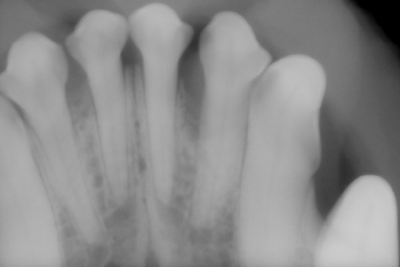

● 正常歯におけるレントゲンの撮影と読影法

ほぼ正常のデジタルレントゲン画像

( 無麻酔にて撮影 )

黄色のラインにて歯槽骨をトレースしております。このトレースラインにより、4番と5番の間は歯周病による50%歯槽骨の融解が認められることがわかります。その他の部位に関しましてはほぼ正常です。